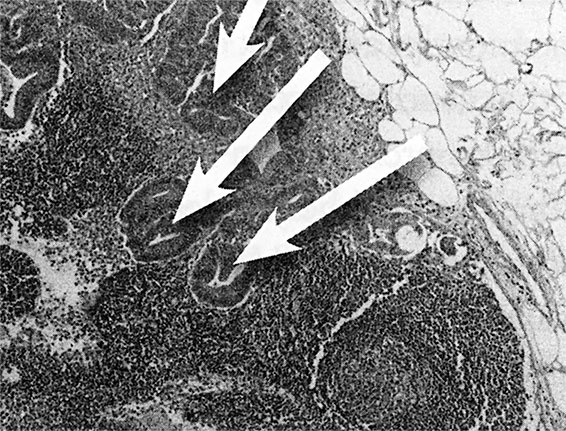

Но такой взгляд на рак на молекулярном уровне не является единственным полезным инструментом в подборе лечения. Для меня рак (рис. 4) выглядит примерно так:

В. Рак в лимфоузле под микроскопом

Вот мы видим А – печень с раком толстой кишки, что правильнее назвать «метастазы рака толстой кишки в печень». Рак переместился, метастазировал, из толстой кишки в печень, что подтверждается белыми образованиями на снимке. Б – томограмма другой печени, пораженной раком толстой кишки («метастазы рака толстой кишки в печень»). Обратите внимание на пять круглых темных образований в левой части изображения. И В – изображение рака толстой кишки в лимфоузле под микроскопом («метастазы рака толстой кишки в лимфоузел»). Пояснение: «рак толстой кишки», который метастазировал в легкие, не будет называться «рак легких». Это все еще рак толстой кишки и выглядит он как рак толстой кишки.